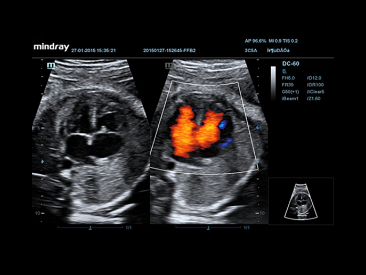

Smart OB?

Auto measurement of fetal parameters: trace and calculate the BPD, OFD, HC, AC and FL on a single click.

?

Smart-NT

Auto-trace tube .swfty edge with measurement result.

iTouch?

Gain instant auto image optimization in B, Color and PW Modes on the click of a single key.